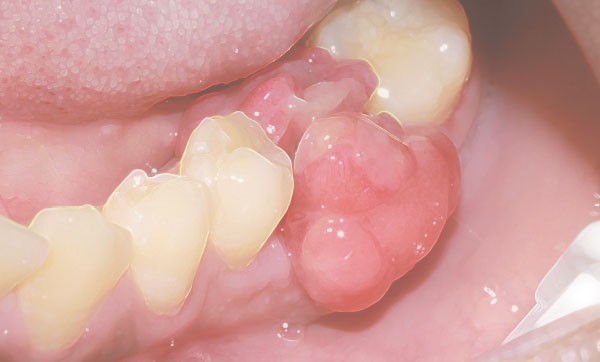

De nombreuses tumeurs bénignes sont retrouvées dans la cavité orale. La plus fréquente est l’épulis. C’est une pseudo-tumeur gingivale dont la principale forme est l’épulis inflammatoire. Le diagnostic se fait face à une tumeur gingivale, généralement hémorragique, en bissac (fig. 6a et b), avec une cause irritative retrouvée (racines résiduelles, tartre, restauration débordante…). Chez la femme enceinte, on retrouve des épulis dits gravidiques…